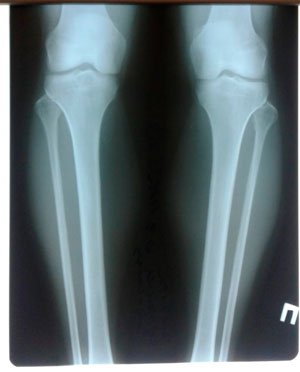

Дата операции - 15.07.2019г.

Дата снятия аппаратов - 15.10.2019г.

Срок сращения 90 дней.